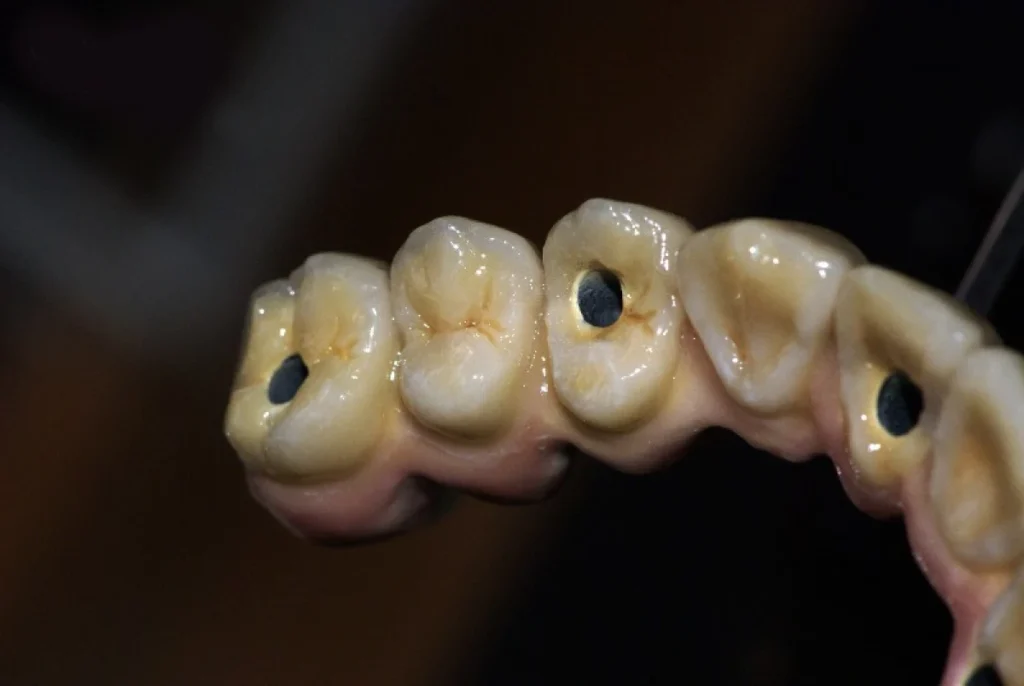

5. Prothèses vissées et scellées

Selon la situation clinique et les besoins spécifiques du patient, une prothèse conjointe peut être fixée de deux manières principales : vissée ou scellée.

Prothèse vissée :

- Retrait facile lors d’un contrôle ou d’un ajustement.

- Maintenance simplifiée en cas de réparation.

- Grande accessibilité pour le praticien.

Prothèse scellée :

- Esthétique discrète grâce à l’absence de vis apparente.

- Sensation plus naturelle pour le patient.

- Solution durable et stable sur le long terme.

Ces deux options répondent à des indications différentes, et notre rôle est d’accompagner le praticien dans ce choix.